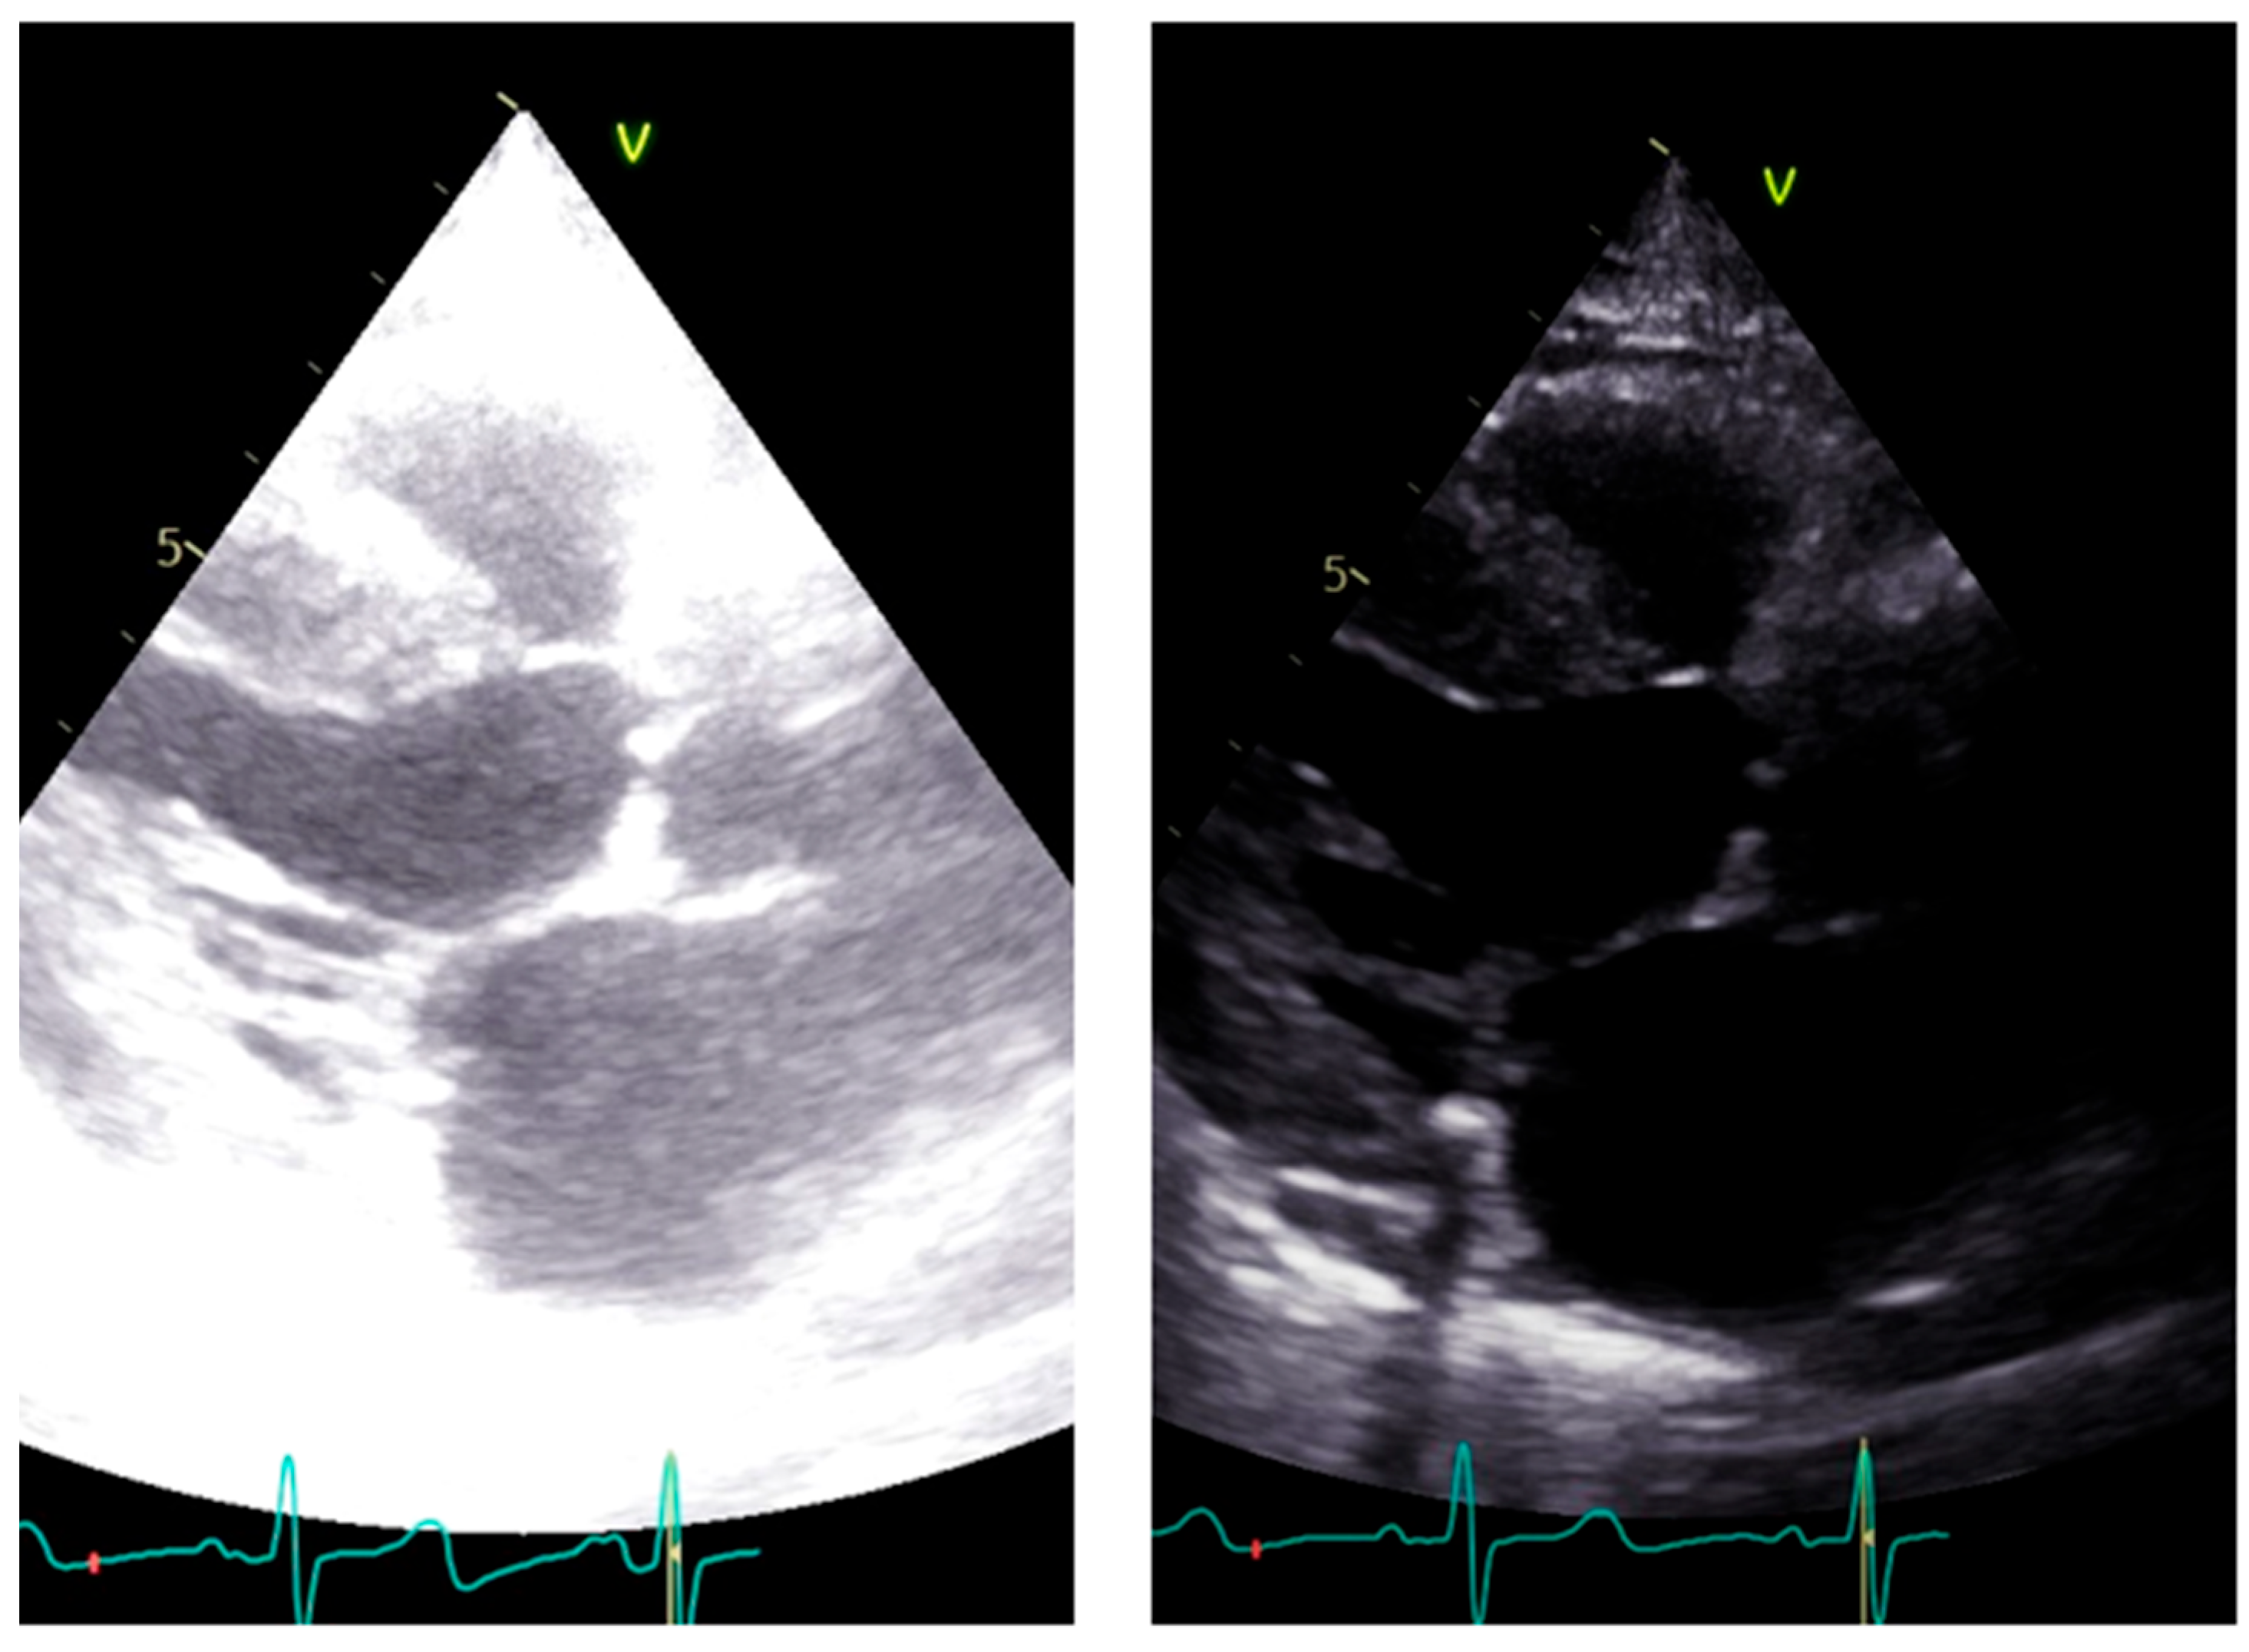

LVOT diameter. The accurate two-dimensional (2D) measurement of LVOT is crucial when assessing AS, as it represents a significant potential source of error in calculating the aortic valve area (AVA) using the continuity equation [15,16,17]. The LVOT measurement is squared within the continuity equation, so any small error in measurement is significantly amplified [18,19]. LVOT diameter should be measured in mid-systole [20]. Mid-systole is the point of the cardiac cycle when the shape of the aortic annulus becomes most circular, and its area becomes maximal. However, for the LVOT, there is no evidence of shape variation from oval to circular throughout systole. Nonetheless, mid-systole should be identified as the frame at half of the total number of frames available between the aortic opening and closure. In this mid-systolic frame, LVOT is measured from the inner edge to the inner edge of the septal endocardium to the anterior mitral leaflet, parallel to the plane of the aortic valve [20]. If a long-axis view is not available, it is not recommended to measure the LVOT from apical views. It is important to recognize that during image acquisition, the parasternal long-axis view provides better axial resolution, whereas the LVOT apical view relies on lateral resolution, which is a limiting factor. It is important to recognize that after the identification of a correct long axis, imaging resolution improvement is fundamental. Axial resolution, as said before, is the most precise of the other two resolutions, lateral and elevational. Thus, quantitative measurements are made most reliably using data derived from a perpendicular alignment. In order to improve axial resolution, higher frequencies should be used. In addition, harmonic imaging is always recommended in that it improves endocardial definition [21]. Gain controls, which adjust the displayed amplitude of the received signals, should be corrected because excessive gain settings can cause “blooming” of the echoes (Figure 3, left panel), leading to a significant underestimation of the LVOT diameter. Conversely, by lowering too much, the gain prevents proper visualization of the anterior endocardium, resulting in an overestimation of the LVOT diameter (Figure 3, right panel).

Figure 3. Over gain (left panel) and lower gain (right panel) in the long-axis view along the same patient.

Figure 4. Measurement of LVOT in the presence of calcium. Left panel: incorrect measurement including calcium; right panel: correct measurement excluding calcium.